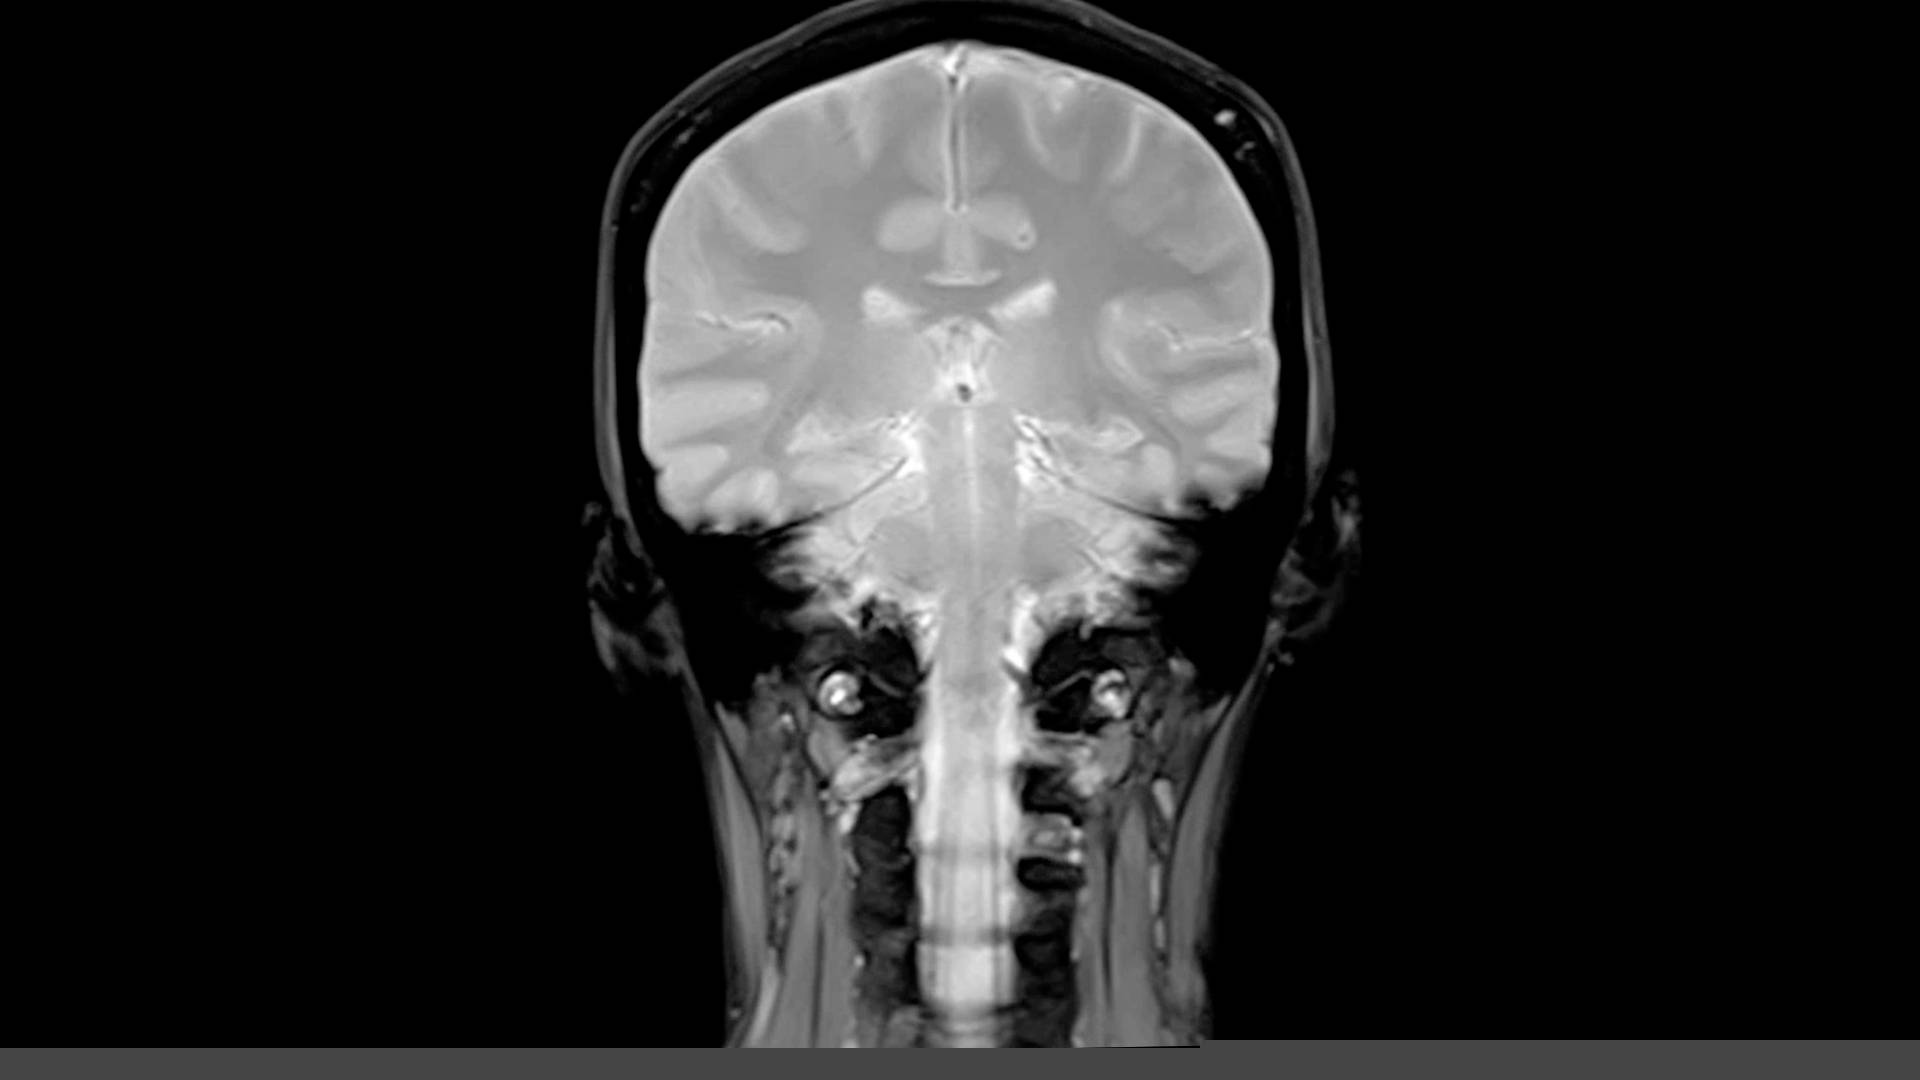

Το πρώτο στοιχείο ήρθε από έναν άνδρα, ο οποίος είχε τη μετάλλαξη που προκαλεί κίνδυνο για Αλτσχάιμερ αλλά και ένα αντίγραφο της Christchurch. Μια ακτινογραφία εγκεφάλου που έκανε όταν ήταν 51 ετών και διαγνώστηκε με ήπια γνωστική εξασθένηση αποκάλυψε ότι ο εγκέφαλός του είχε αυξημένα επίπεδα πλακών της πρωτεΐνης του β-αμυλοειδούς, κάτι που αποτελεί σημάδι Αλτσχάιμερ.